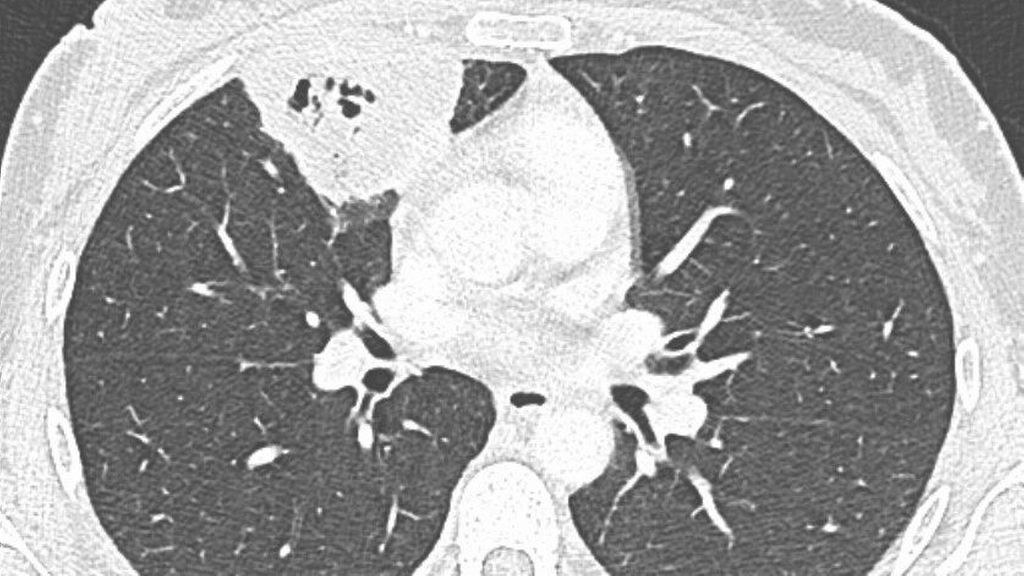

Unter der eskalierten Immunsuppression kam es zu einer bemerkenswerten klinischen und radiologischen Besserung. Die Entzündungswerte normalisierten sich rasch und sowohl die pulmonalen Infiltrate (Abb.2) als auch der Pseudotumor an der Schädelbasis begannen in der Bildgebung zu schrumpfen. Auch die neurologischen Defizite zeigten sich rückläufig, wenngleich dieser Prozess deutlich langsamer verlief.

Abb. 2: Thorax-CT vor (links) und nach Einleitung der Therapie (Quelle: Universitätsklinik für Radiologie Innsbruck)